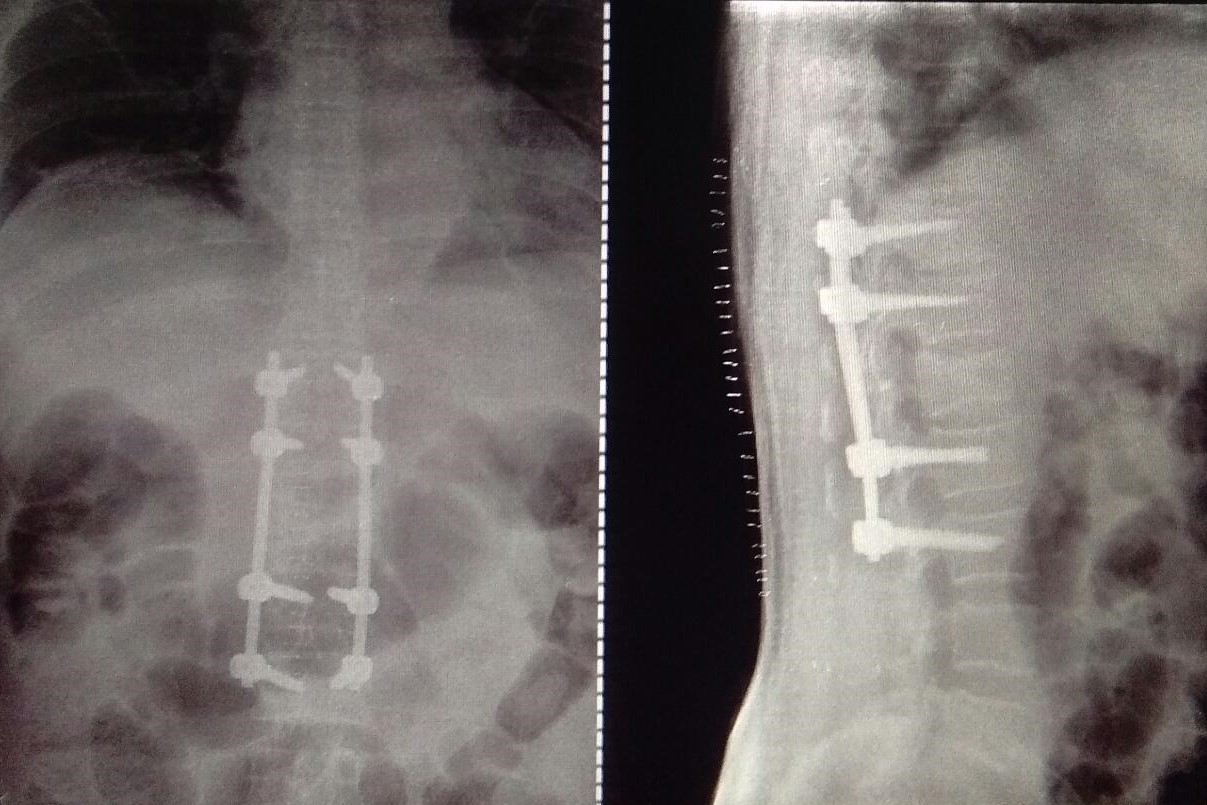

Spine Surgery